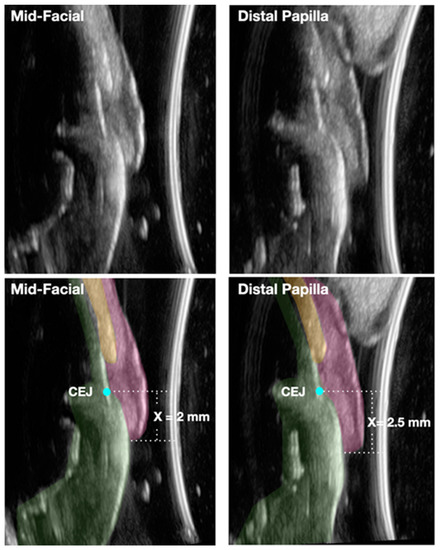

- Tattan, M.; Sinjab, K.; Lee, E.; Arnett, M.; Oh, T.J.; Wang, H.L.; Chan, H.L.; Kripfgans, O.D. Ultrasonography for chairside evaluation of periodontal structures: A pilot study. J. Periodontol. 2020, 91, 890–899. [Google Scholar] [CrossRef] [PubMed]

- Nguyen, K.-C.T.; Le, L.H.; Kaipatur, N.R.; Major, P.W. Imaging the cemento-enamel junction using a 20-MHz ultrasonic transducer. Ultrasound Med. Biol. 2016, 42, 333–338. [Google Scholar] [CrossRef] [PubMed]

- With the aid of novel noninvasive and chairside ultrasound imaging and the high-magnification operating microscope, accurate and reproducible assessment of the negative gingival recession can become a reality that allows for early detection and intervention of periodontitis. These technologies could also prove to be valuable clinical and research tools in accurately detecting the amount of clinical attachment gain resulting from periodontal therapeutic modalities.